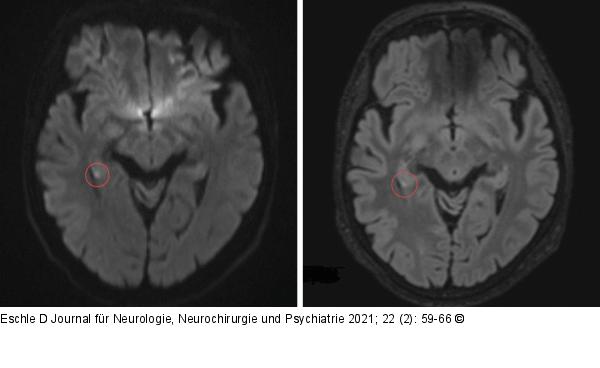

Abbildung 1: Punktförmige MRT-Läsion Exemplarische Magnetresonanztomographie mit einer typischen punktförmigen Läsion im rechten Hippokampus (Kreis) bei transienter globaler Amnesie: links: axiale DWI-Sequenz, rechts: FLAIR-Bild. ADC- und T2-Sequenzen nicht abgebildet (Bilder aus der Sammlung des Autors). |

Exemplarische Magnetresonanztomographie mit einer typischen punktförmigen Läsion im rechten Hippokampus (Kreis) bei transienter globaler Amnesie: links: axiale DWI-Sequenz, rechts: FLAIR-Bild. ADC- und T2-Sequenzen nicht abgebildet (Bilder aus der Sammlung des Autors). |